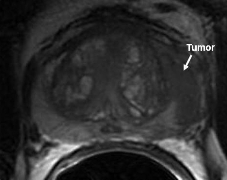

Figure 1 is a 48 year old male with a PSA of 5.23 ng/ml and biopsy proven prostate carcinoma of Gleason score 10 (5.5).

Figure 1a: Diffusion MRI scan showing the tumor (white arrow)